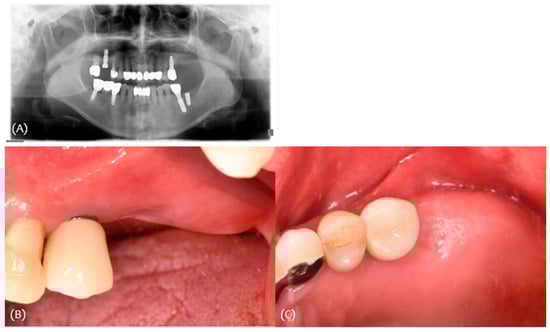

3.1. Case 1

3.2. Case 2

3.3. Case 3